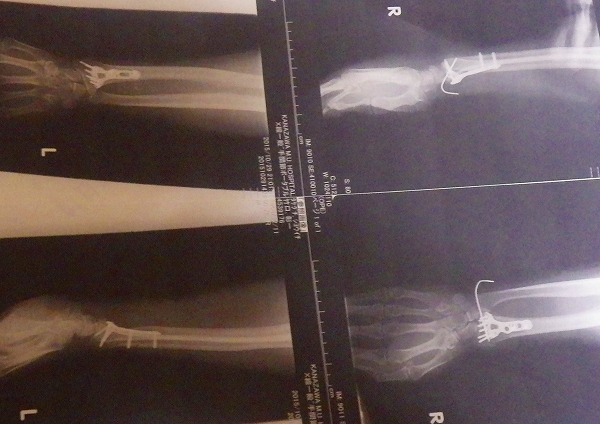

元々のブレーキ強化計画の経緯が 手の怪我による 握力低下を補うモノ

であったことから この仕様でも十分でした

手の怪我 今でも痛みますし

普通にバイクには乗れますが トライアルのコンペはもうキツイでしょうね